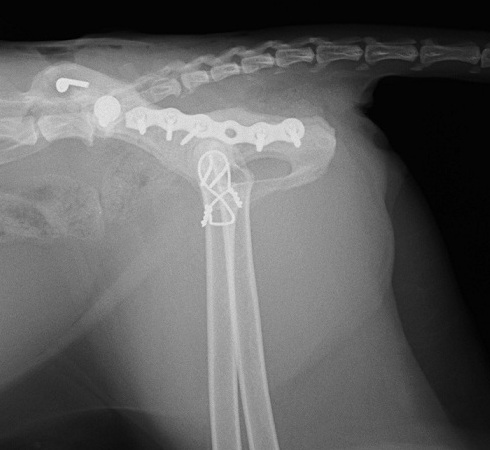

レントゲン検査で、左側の仙腸関節離断と同側の寛骨臼の骨折をしていることがわかりました。 寛骨臼の骨折は坐骨からの斜骨折を伴うもので、人の下顎骨骨折に用いられるMatrix Mandibleというプレートで整復しました。

高齢でしたが術後経過は良好で、椅子にも飛び上がれるようになりました。

手術後レントゲン側画像

レントゲン検査で、左側の仙腸関節離断と同側の寛骨臼の骨折をしていることがわかりました。 寛骨臼の骨折は坐骨からの斜骨折を伴うもので、人の下顎骨骨折に用いられるMatrix Mandibleというプレートで整復しました。

高齢でしたが術後経過は良好で、椅子にも飛び上がれるようになりました。

手術後レントゲン側画像